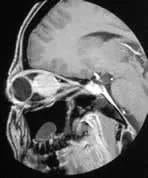

Right Orbital Mass

A patient presents with right-sided ocular pain and parietal headaches.

A large ovoid intraconal mass is shown in the right orbit. It does not extend intracranially or into the optic canal and it is transversed by the optic nerve. The appearances are most likely to be those of a glioma.